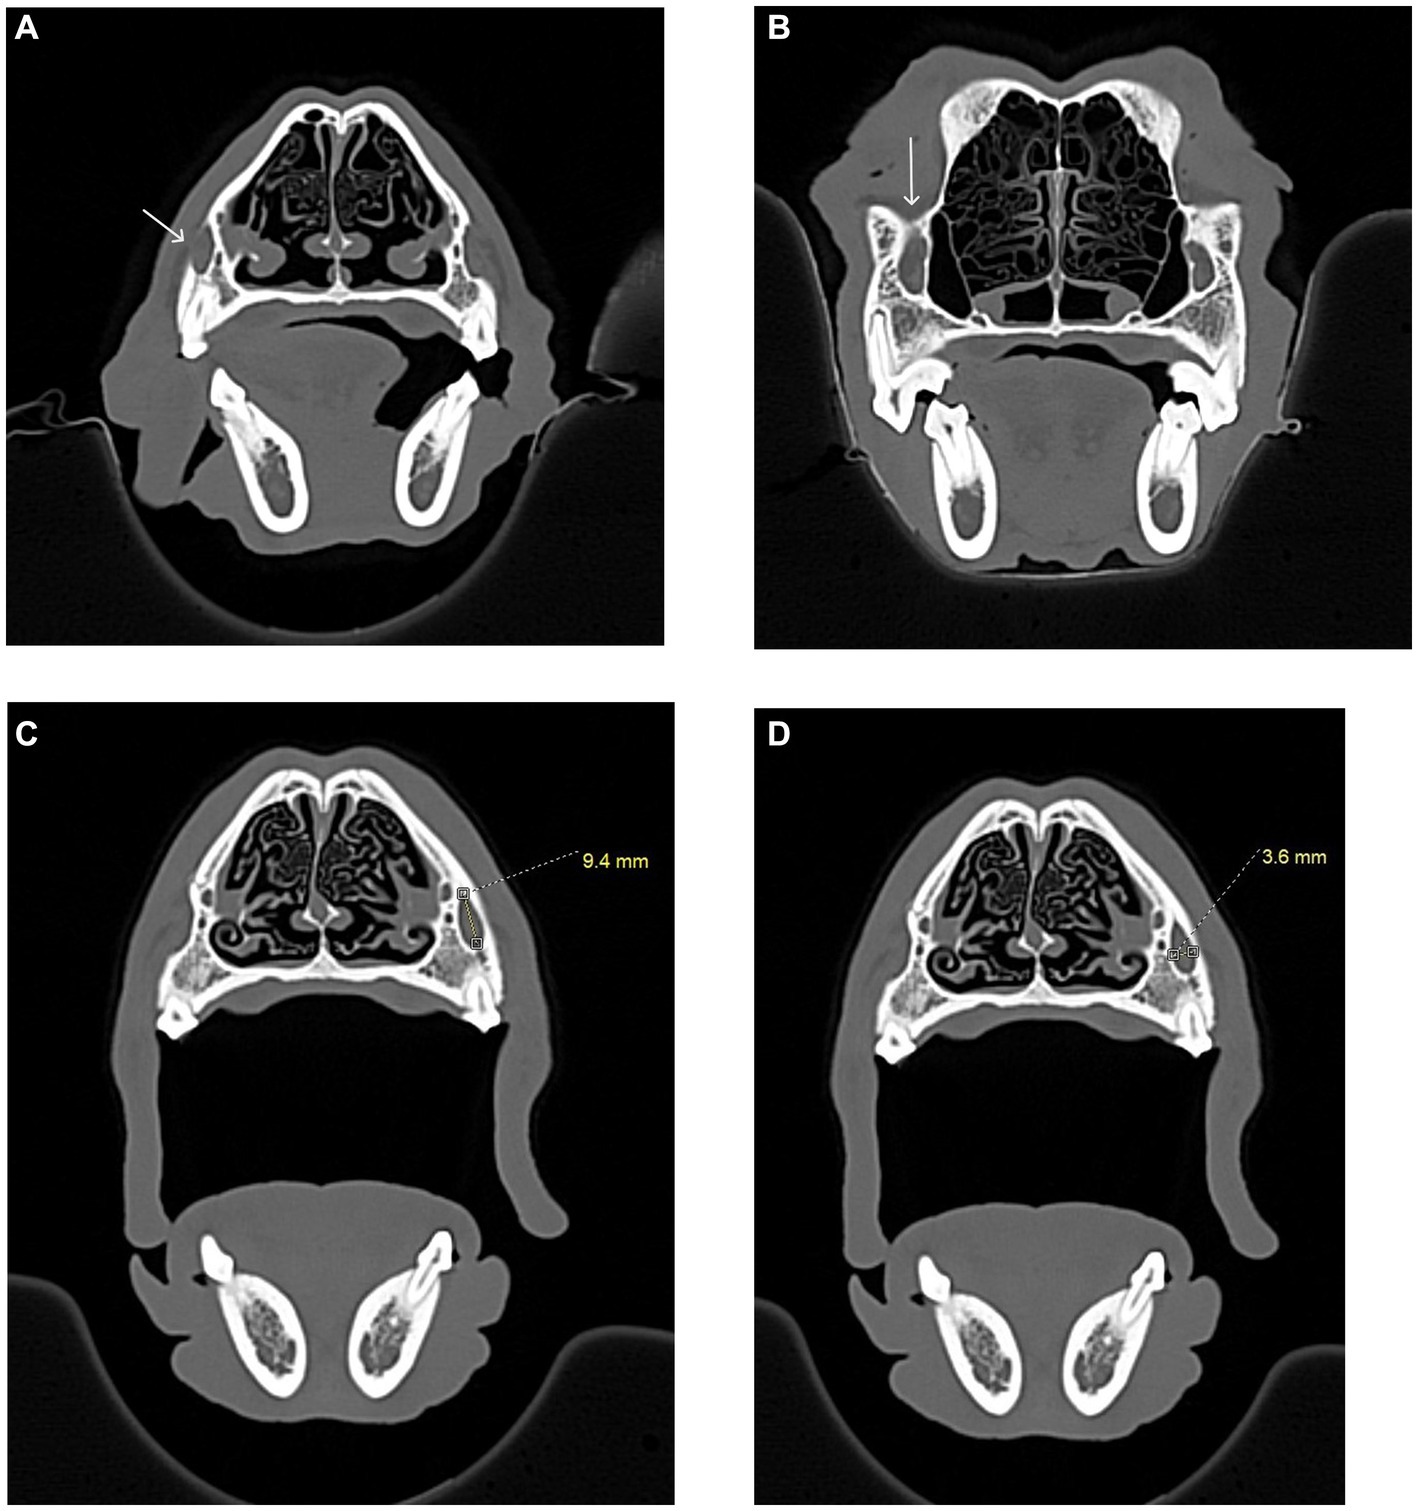

Figure 4

CT scan images showing lateral and transverse views of a dog skull showing measurements between the maxillary first molar root apex and the eye. A measurement of twenty-nine millimeters is highlighted.Alt-text 4B CT images showing lateral and transverse views of a dog skull showing measurements between the maxillary second molar root apex and the eye. A measurement of thirty-one millimeters is highlighted. Alt-text 4C CT scan images showing lateral and transverse views of a cat skull showing the root apex of the maxillary fourth premolar centered in a set of crosshairs. CT image of the lateral view of a cat skull showing measurements between a tooth root apex and the eye. A measurement of four point three millimeters is highlighted.

Figure 4. CT images showing how measurements, in millimeters, were collected from the apices of the maxillary first molar tooth and second molar tooth to the globe in dogs, and from the maxillary fourth premolar tooth to the globe in cats. (A) Distance from the right maxillary first molar tooth palatal root apex to the globe using both the sagittal (left) and transverse (right) views simultaneously for accuracy. (B) Distance from the right maxillary second molar tooth distal buccal root apex to the globe using both the sagittal (left) and transverse (right) views simultaneously for accuracy. (C) Transverse (left) and sagittal (right) views were used to confirm the right maxillary fourth premolar tooth distal root apex. The root apex is visible in the crosshairs on both the transverse and sagittal views. (D) After confirming the right maxillary fourth premolar tooth distal root apex (C), the distance from the root apex to the closest surface of the globe was measured.